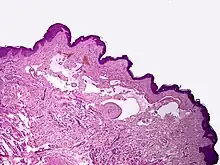

Proliferating lymphangioma, H&E stain. Sometimes endothelial cells begin to divide excessively.

In 1976, Whimster studied the pathogenesis of lymphangioma circumscriptum, finding lymphatic cisterns in the deep subcutaneous plane are separated from the normal network of lymph vessels. They communicate with the superficial lymph vesicles through vertical, dilated lymph channels. Whimster theorized the cisterns might come from a primitive lymph sac that failed to connect with the rest of the lymphatic system during embryonic development.

A thick coat of muscle fibers that cause rhythmic contractions line the sequestered primitive sacs. Rhythmic contractions increase the intramural pressure, causing dilated channels to come from the walls of the cisterns toward the skin. He suggested that the vesicles seen in lymphangioma circumscriptum are outpouchings of these dilated projecting vessels. Lymphatic and radiographic studies support Whimsters observations. Such studies reveal that big cisterns extend deeply into the skin and beyond the clinical lesions. Lymphangiomas that are deep in the dermis show no evidence of communication with the regular lymphatics. The cause for the failure of lymph sacs to connect with the lymphatic system is not known.[4]

Microscopically, the vesicles in lymphangioma circumscriptum are greatly dilated lymph channels that cause the papillary dermis to expand. They may be associated with acanthosis and hyperkeratosis. There are many channels in the upper dermis which often extend to the subcutis (the deeper layer of the dermis, containing mostly fat and connective tissue). The deeper vessels have large calibers with thick walls which contain smooth muscle. The lumen is filled with lymphatic fluid, but often contains red blood cells, lymphocytes, macrophages, and neutrophils. The channels are lined with flat endothelial cells. The interstitium has many lymphoid cells and shows evidence of fibroplasia (the formation of fibrous tissue). Nodules (A small mass of tissue or aggregation of cells) in cavernous lymphangioma are large, irregular channels in the reticular dermis and subcutaneous tissue that are lined by a single layer of endothelial cells. Also an incomplete layer of smooth muscle also lines the walls of these channels. The stroma consists of loose connective tissue with a lot of inflammatory cells. These tumors usually penetrate muscle. Cystic hygroma is indistinguishable from cavernous lymphangiomas on histology.[4]